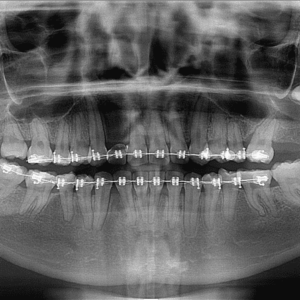

Radiografía Panorámica en Studio Digital Imaging

La radiografía panorámica dental es una técnica de imagenología fundamental en odontología que proporciona una vista amplia y detallada de toda la estructura oral. A diferencia de las radiografías dentales periapicales, que muestran áreas específicas de la boca, la radiografía panorámica ofrece una visión global de los dientes, mandíbulas, huesos faciales y otras estructuras adyacentes...